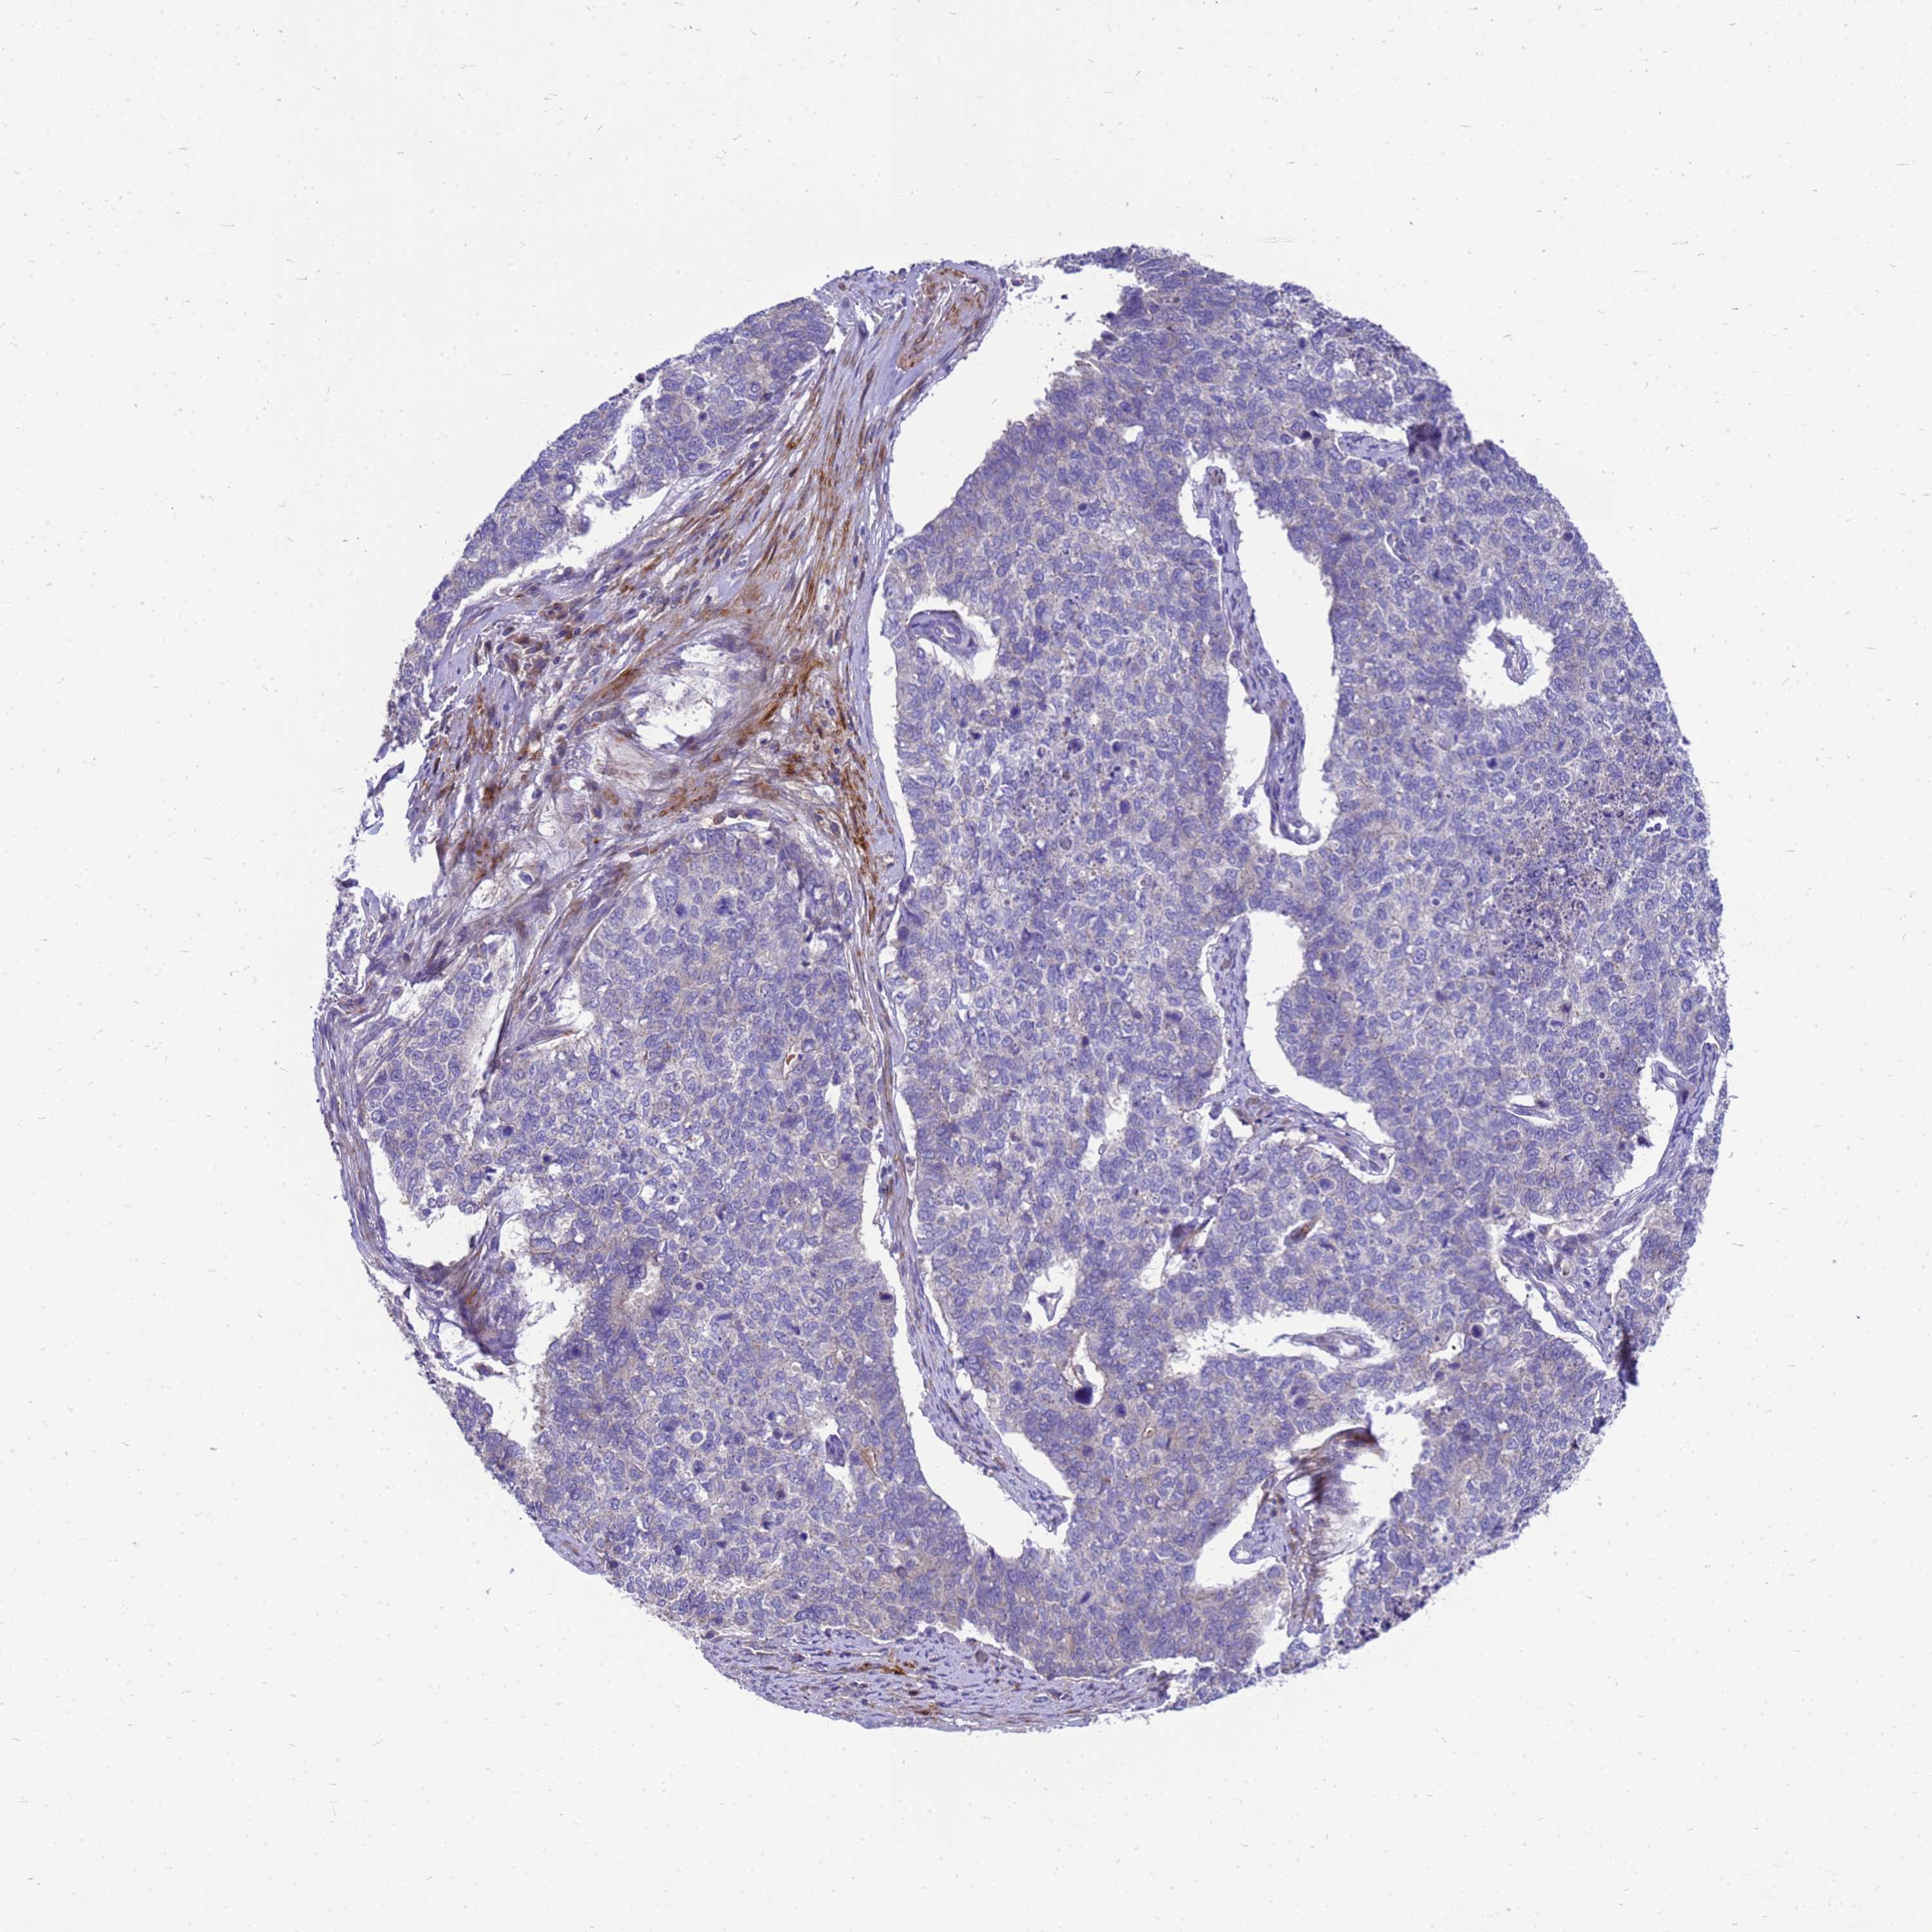

CERVICAL CANCER - Protein expressioni

A mouse-over function shows sample information and annotation data. Click on an image to view it in a full screen mode. Samples can be filtered based on level of antibody staining by selecting one or several of the following categories: high, medium, low and not detected. The assay and annotation is described here.

Note that samples used for immunohistochemistry by the Human Protein Atlas do not correspond to samples in the TCGA dataset.

Antibody stainingi

Antibody staining in the annotated cell types in the current human tissue is reported as not detected, low, medium, or high, based on conventional immunohistochemistry profiling in selected tissues. This score is based on the combination of the staining intensity and fraction of stained cells.

Each image is clickable and will lead to virtual microscopy that enables deeper exploration of all samples and also displays staining intensity scores, fraction scores and subcellular localization as well as patient and tissue information for each sample.

Antibody HPA021007

Staining

High

Medium

Low

Not detected

Intensity

Strong

Moderate

Weak

Negative

Quantity

>75%

75%-25%

<25%

None

Location

Nuclear

Cytoplasmic/membranous

Cytoplasmic/membranous,nuclear

Squamous cell carcinoma, NOS

Adenocarcinoma, NOS